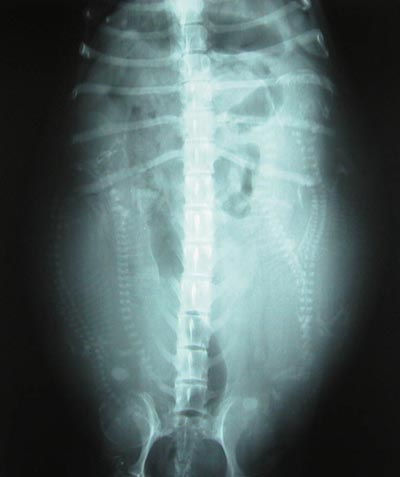

今日は待ちに待ったレントゲン撮影日。

病院に着いて早速レントゲン撮影をした。

写真を見ると背骨らしいものが写っているのがわかった。

先生の「4匹いますよ。」の言葉に思わず

「やった〜!」と叫んでしまった。

お腹の中の子供はもういつ産まれてもおかしくない

大きさということだ。

幸い、キャンディーは産道が広いらしく出産には

適していると言われた。